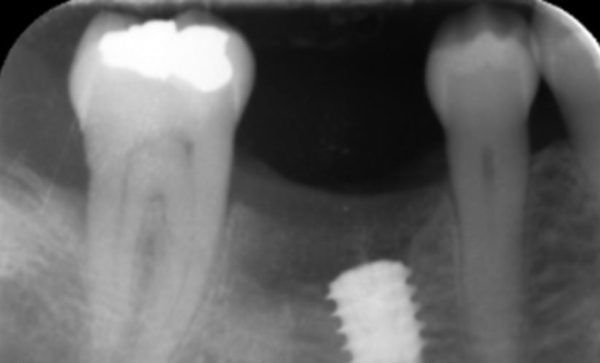

Case 12